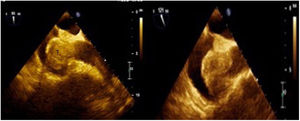

En la ecografía transesofágica (ETE; fig. 1) se aprecia una masa multilobulada que ocupa dos tercios de la aurícula derecha, de 48×36mm, con un área de 17cm2, con base ancha, adosada al septum interauricular hacia el fondo de la aurícula derecha. Esta masa obstruye la desembocadura de la vena cava superior en casi su totalidad, y dicha vena se observa dilatada, con 25mm de diámetro. La ecografía transtorácica muestra una masa en la aurícula derecha (fig. 1), cavidades cardiacas con geometría y diámetros normales, función sistólica y diastólica conservada en reposo, fracción de eyección del ventrículo izquierdo del 68%. Válvulas cardíacas de morfología normal, insuficiencia tricúspide ligera, grosor parietal y pericardio normales, sin derrame pericárdico.